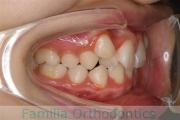

No.19V-044

- 上顎前突

- 13歳

- 女性

- 上:

- 44

- 下:

- 8558

- 主な使用装置:

- FEA

- 治療にかかった費用:

- 85万円

出っ歯を治したいということで小学生の時に来院されました。中学生になるまで経過観察をして、診断、上下左右から小臼歯を抜歯してマルチブラケット法にて治療を行いました。2年強、30回程度の通院が必要でした。

口元の突出感も大きく改善しています。

- ≫治療前